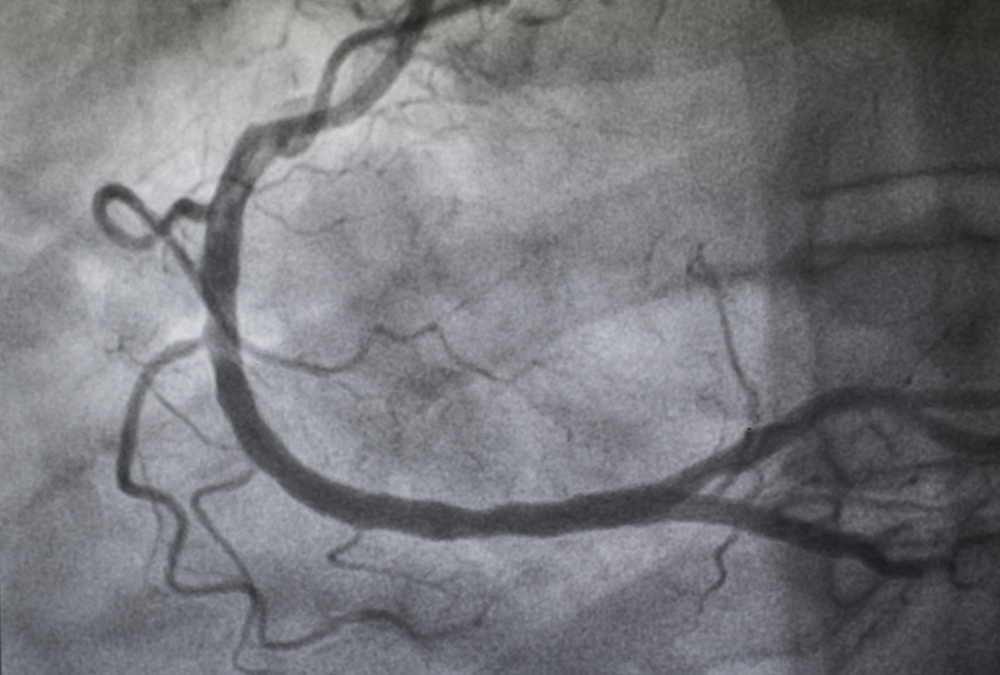

- МСКТ с контрастированием, ангиопульмонография, перфузионная сцинтиграфия – эти исследования легких позволяют получать снимки, которые точно устанавливают сосудистое происхождение мальформации и визуализируют ее питающие и дренирующие сосуды.